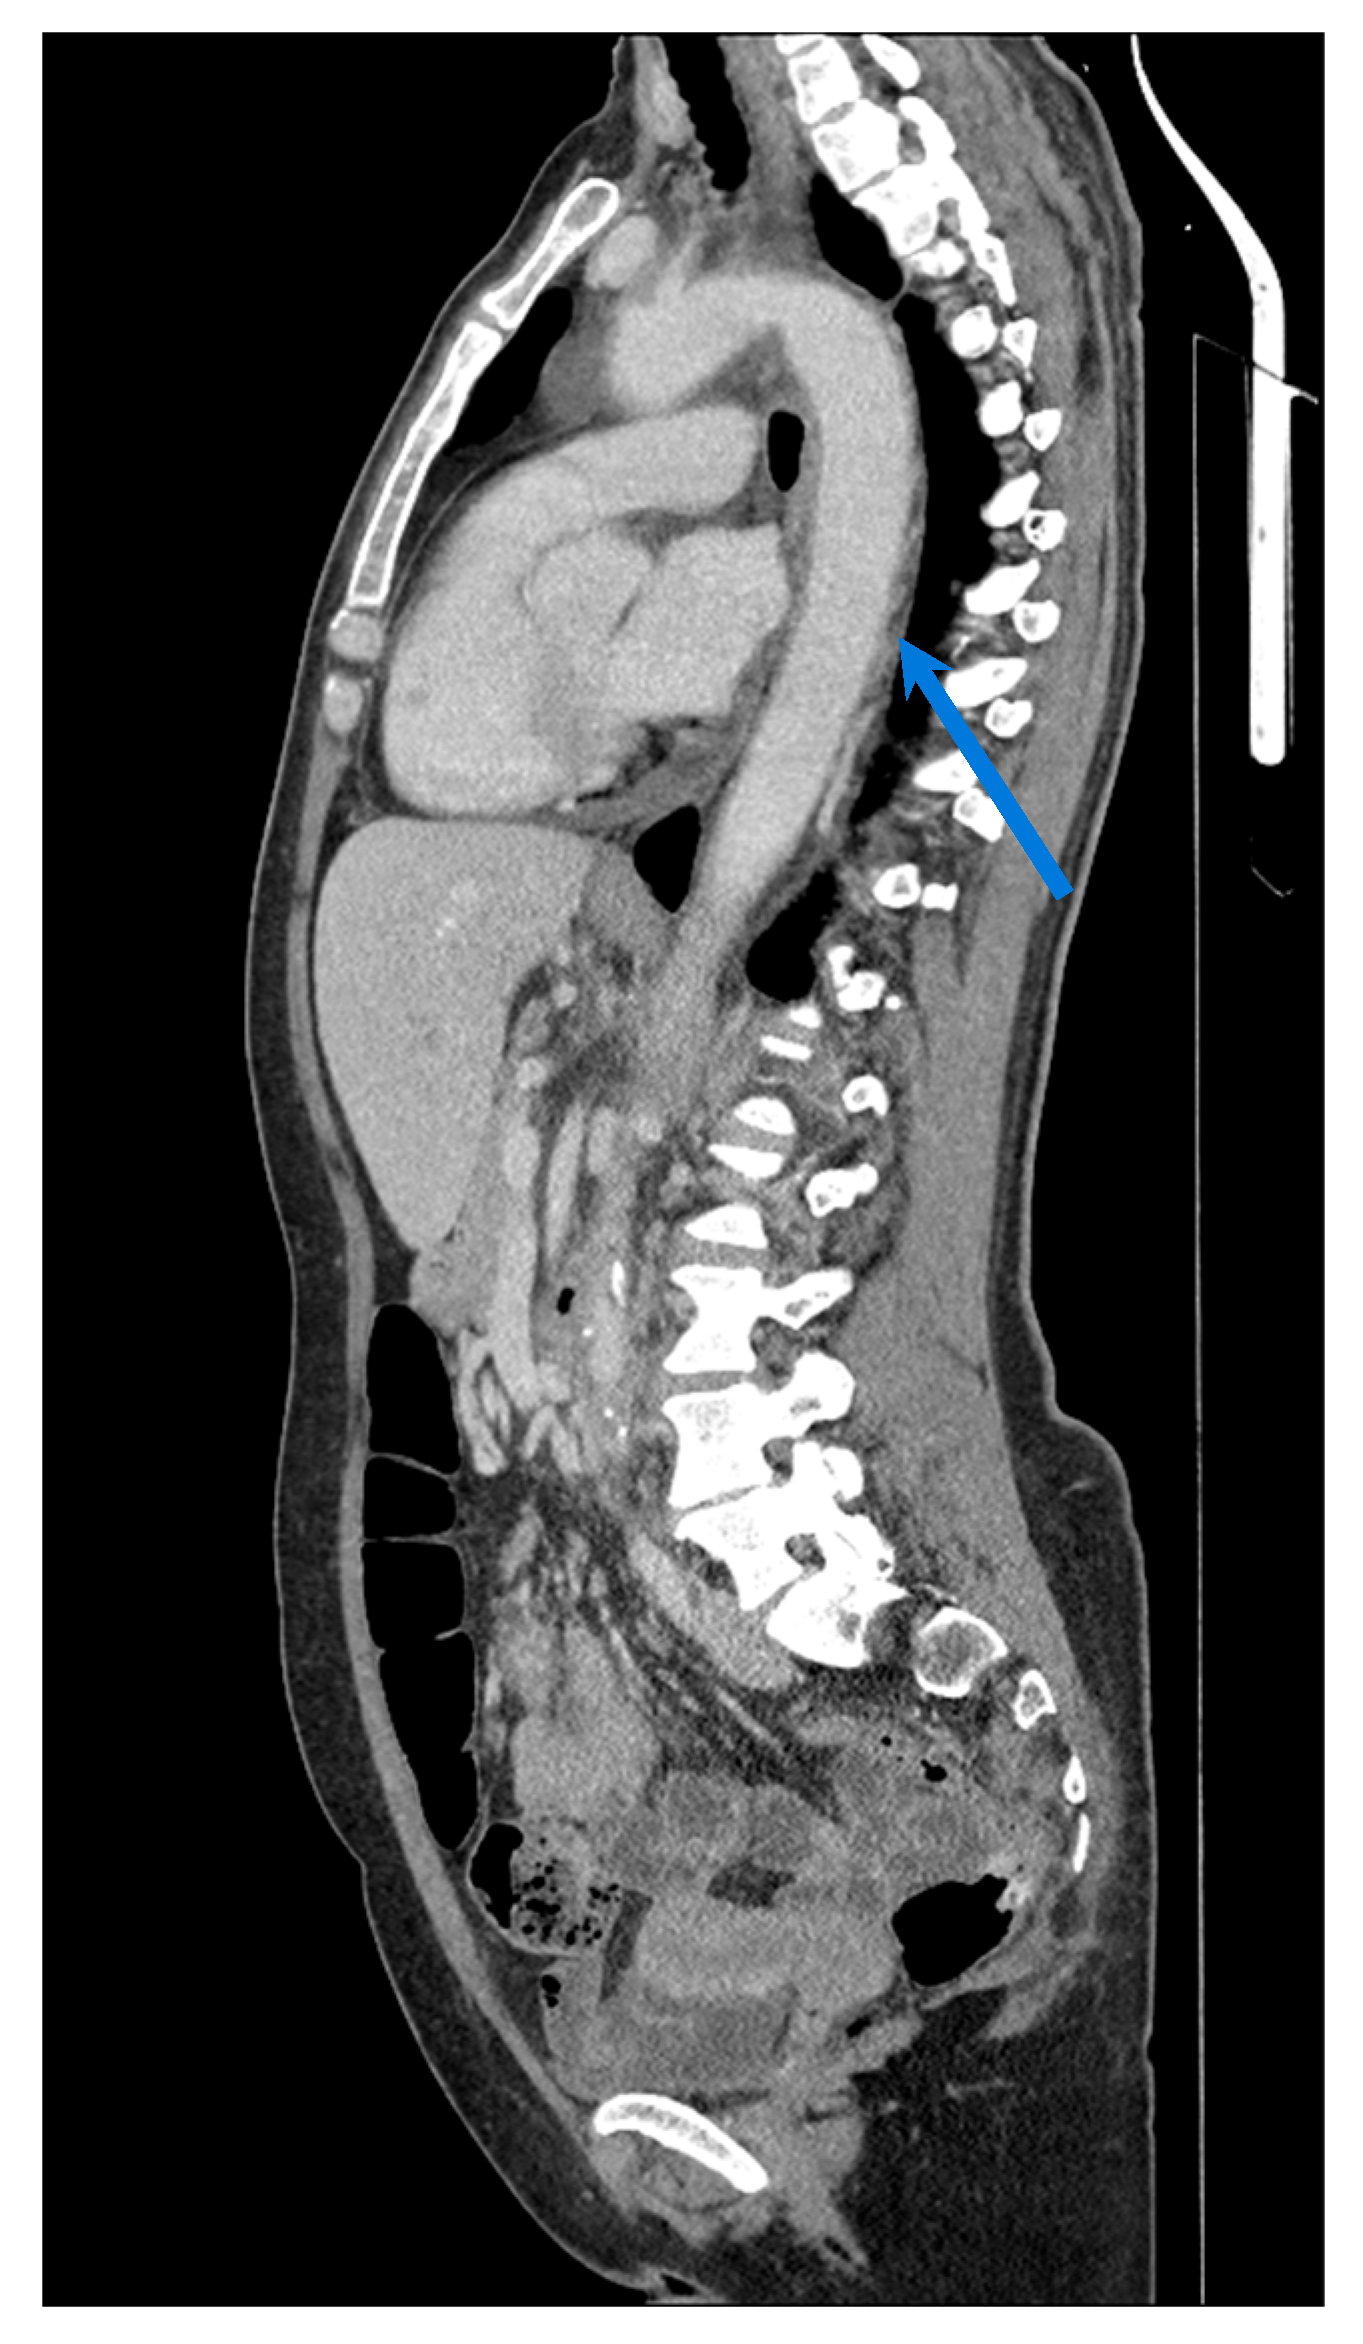

3. Magnetic Resonance Imaging

3.2. Takayasu Arteritis